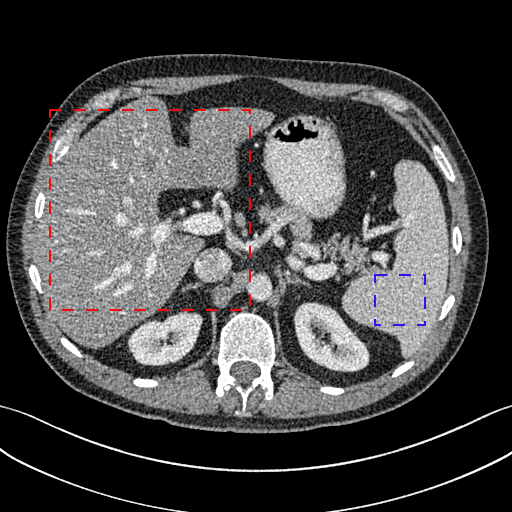

To show the denoising effect of the selected networks, we took two representative slices as shown in Figs. 5 and 7. And Figs. 6 and 8 are the zoomed regions-of-interest (ROIs) marked by the red rectangles in Figs. 5 and 7. All the networks demonstrated certain denoising capabilities. However, CNN-MSE blurred the images and introduced waxy artifacts as expected, which are easily observed in the zoomed ROIs in Figs. 6e and 8e. WGAN-MSE was able to improve the result of CNN-MSE by avoiding over-smooth but minor streak artifacts can still be observed especially compared to CNN-VGG and WGAN-VGG. Meanwhile, using WGAN or GAN alone generated stronger noise (Figs. 6g and 8g) than the other networks enhanced a few white structures in the WGAN/GAN generated images, which are originated from the low dose streak artifact in LDCT images, while on the contrary the CNN-VGG and WGAN-VGG images are visually more similar to the NDCT images. This is because the VGG loss used in CNN-VGG and WGAN-VGG is computed in a feature space that is trained previously on a very large natural image dataset [48]. By using VGG loss, we transferred the knowledge of human perception that is embedded in VGG network to CT image quality evaluation. The performance of using WGAN or GAN alone is not acceptable because it only maps the data distribution from LDCT to NDCT but does not guarantee the image content correspondence. As for the lesion detection in these two slices, all the networks enhance the lesion visibility compared to the original noisy low dose FBP images as noise is reduced by the different approaches.

As for iterative reconstruction technique, the reconstruction results depend greatly on the choices of the regularization parameters. The implemented dictionary learning reconstruction (DictRecon) result gave the most aggressive noise reduction effect compared to the network outputs as a result of strong regularization. However, it over-smoothed some fine structures. For example, in Fig. 8, the vessel pointed by the green arrow was smeared out while it is easily identifiable in NDCT as well as WGAN-VGG images. Yet, as an iterative reconstruction method, DictRecon has its advantage over post-processing method. As pointed by the red arrow in Fig 8, there is a bright spot which can be seen in DictRecon and NDCT images, but is not observable in LDCT and network processed images. Since the WGAN-VGG image is generated from LDCT image, in which this bright spot is not easily observed, it is reasonable that we do not see the bright spot in the images processed by neural networks. In other words, we do not want the network to generate structure that does not exist in the original images. In short, the proposed WGAN-VGG network is a post-processing method and information that is lost during the FBP reconstruction cannot easily be recovered, which is one limitation for all the post-processing methods. On the other hand, as an iterative reconstruction method, DictRecon algorithm generates images from raw data, which has more information than the post-processing methods.

To gain more insight into the output images from different approaches, we inspect the statistical properties by calculating the mean CT numbers (Hounsfield Units) and standard deviations (SDs) of two flat regions in Figs. 5 and 7 (marked by the blue rectangles). In an ideal scenario, a noise reduction algorithm should achieve mean and SD to the gold standard as close as possible. In our experiments, the NDCT FBP images were used as gold standard because they have the best image quality in this dataset. As shown in Table III, Both CNN-MSE and DictRecon produced much smaller SDs compared to NDCT, which indicates they over-smoothed the images and supports our visual observation. On the contrary, WGAN produced the closest SDs yet smaller mean values, which means it can reduce noise to the same level as NDCT but it compromised the information content. On the other hand, the proposed WGAN-VGG has outperformed CNN-VGG, WGAN-MSE and other selected methods in terms of mean CT numbers, SDs, and most importantly visual impression.